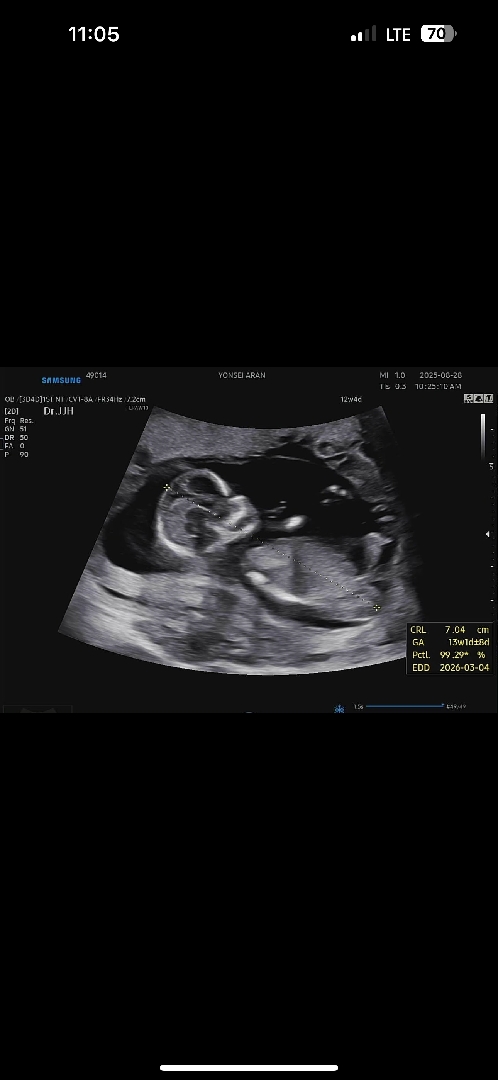

12주차 사진~

12주차인데 크기는13주차래용 우량아 예약ㅋㄷ 사진보면 느낌이딸일거같은데 여러분생각은 어떠세요?